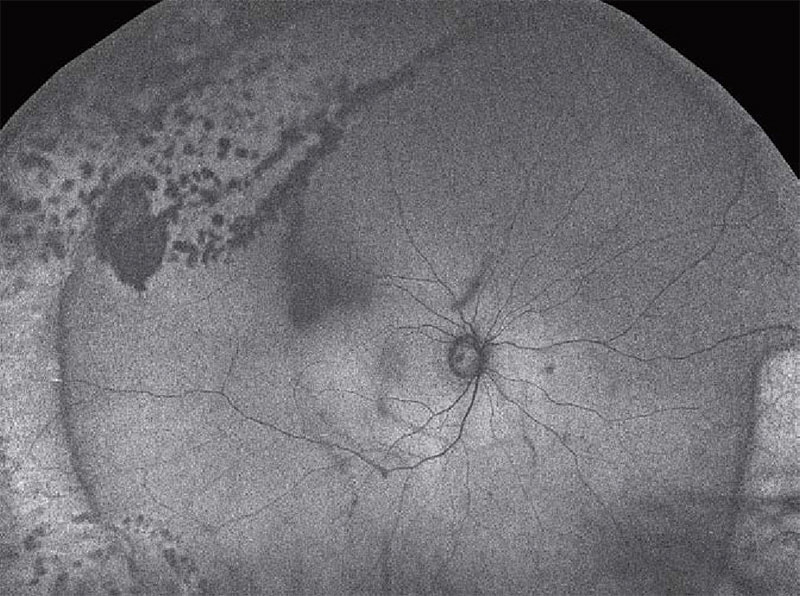

Silverstoneは、UWF Swept Source OCTにより、optomap®上のあらゆる部位の病変を捉えます。

クリック操作で画角200度のoptomap®画像全体を表示することが可能です。

レッドレーザー、グリーンレーザーそれぞれで取得した画像と、それらを合成したカラー画像を個別に表示できます。

レーザー光の波長により深達度が異なるので、病変の部位を判別できます。